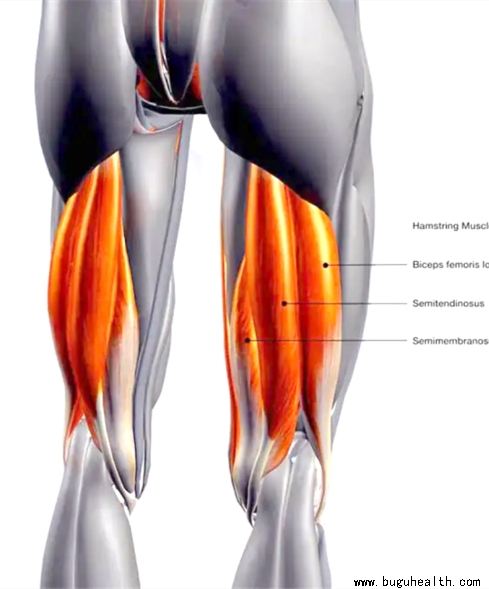

- 手动肌肉测试(Manual muscle testing)在肌骨康复中用于评估肌肉和肌腱生成力量的能力。在康复领域中,肌肉测试是评估肌肉是否存在损伤和缺陷的重要工具,包括肌肉力量,肌肉耐力和肌肉爆发力等。肌肉功能损伤(Impairment)可能是来自于一系列问题,例如肌骨损伤,心血管功能受损,肺功能.....